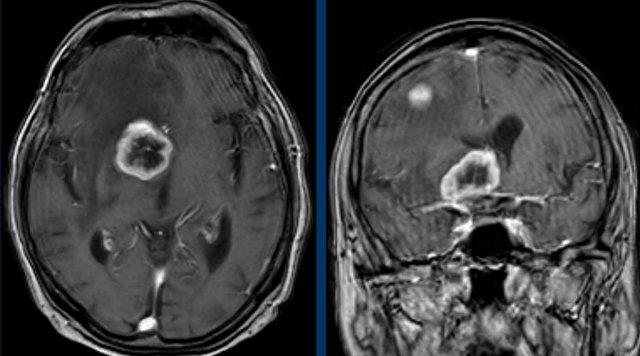

Những hình ảnh này của một người đàn ông 78 tuổi

được biết là có ung thư biểu mô tế bào vảy ở sàn miệng và than phiền về nhìn đôi.

Khi khám thực thể, bệnh nhân mất định hướng và có

rối loạn vận ngôn và hội chứng Horner.

Dựa trên những phát hiện này, chúng tôi cho rằng hội chứng Horner là

do nguyên nhân trung ương.

Hình ảnh

T1 MPRAGE 3D cho thấy một tổn thương ngấm thuốc dạng vòng nhẫn lớn ở vùng đồi thị bên phải và một tổn thương thứ hai ở bán cầu não phải.

Kết luận

Di căn của ung thư biểu mô tế bào vảy.

Thông thường các ung thư biểu mô này không di căn dễ dàng như vậy.

Ở các tầng khác có nhiều di căn hơn (vòng tròn).

Hình minh họa cho thấy mức độ của bệnh lý.